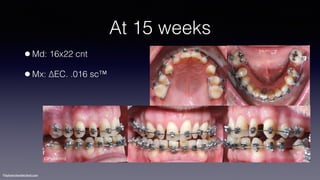

At 15 weeks

•Md: 16x22 cnt

•Mx: ∆EC. .016 sc™